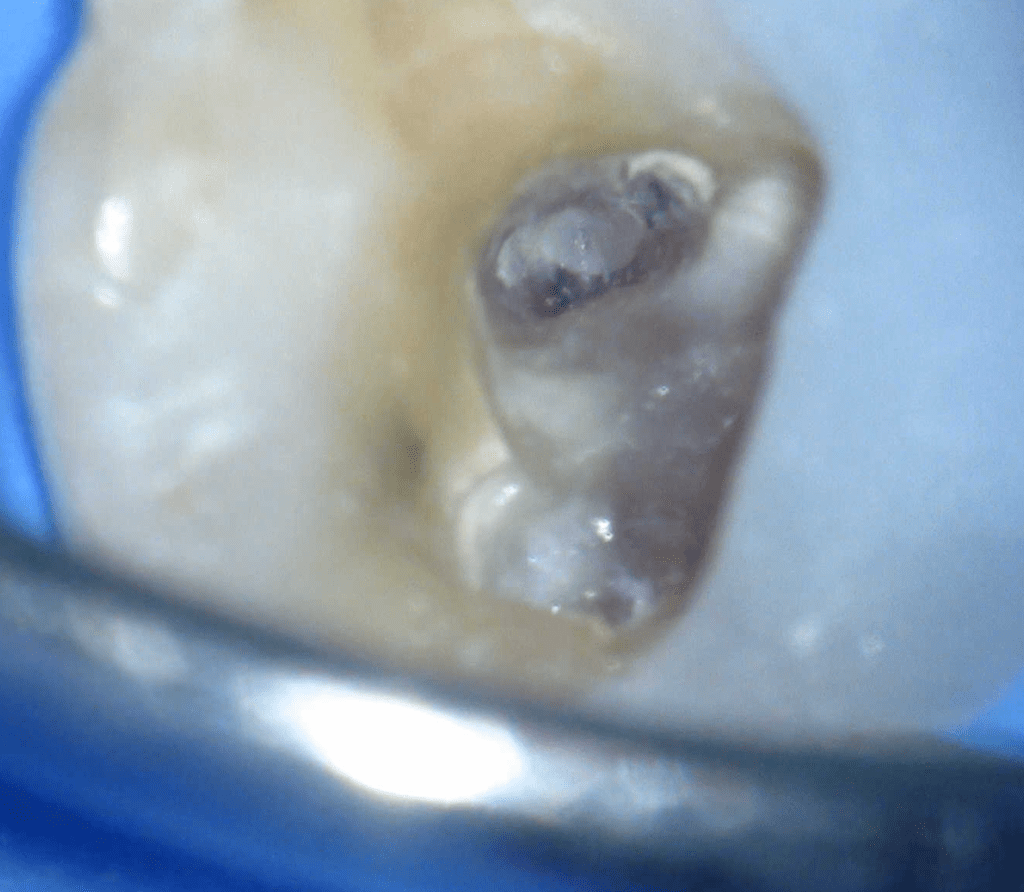

Pulpotomía biodentine + reco preendio